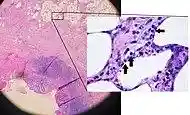

Pathology

Even for clinically certain appendicitis, routine histopathology examination of appendectomy specimens is of value for identifying unsuspected pathologies requiring further postoperative management.[59] Notably, appendix cancer is found incidentally in about 1% of appendectomy specimens.[60]

Pathology diagnosis of appendicitis can be made by detecting a neutrophilic infiltrate of the muscularis propria.

Periappendicitis, inflammation of tissues around the appendix, is often found in conjunction with other abdominal pathology.[61]

Acute suppurative appendicitis with perforation (at right). H&E stain.